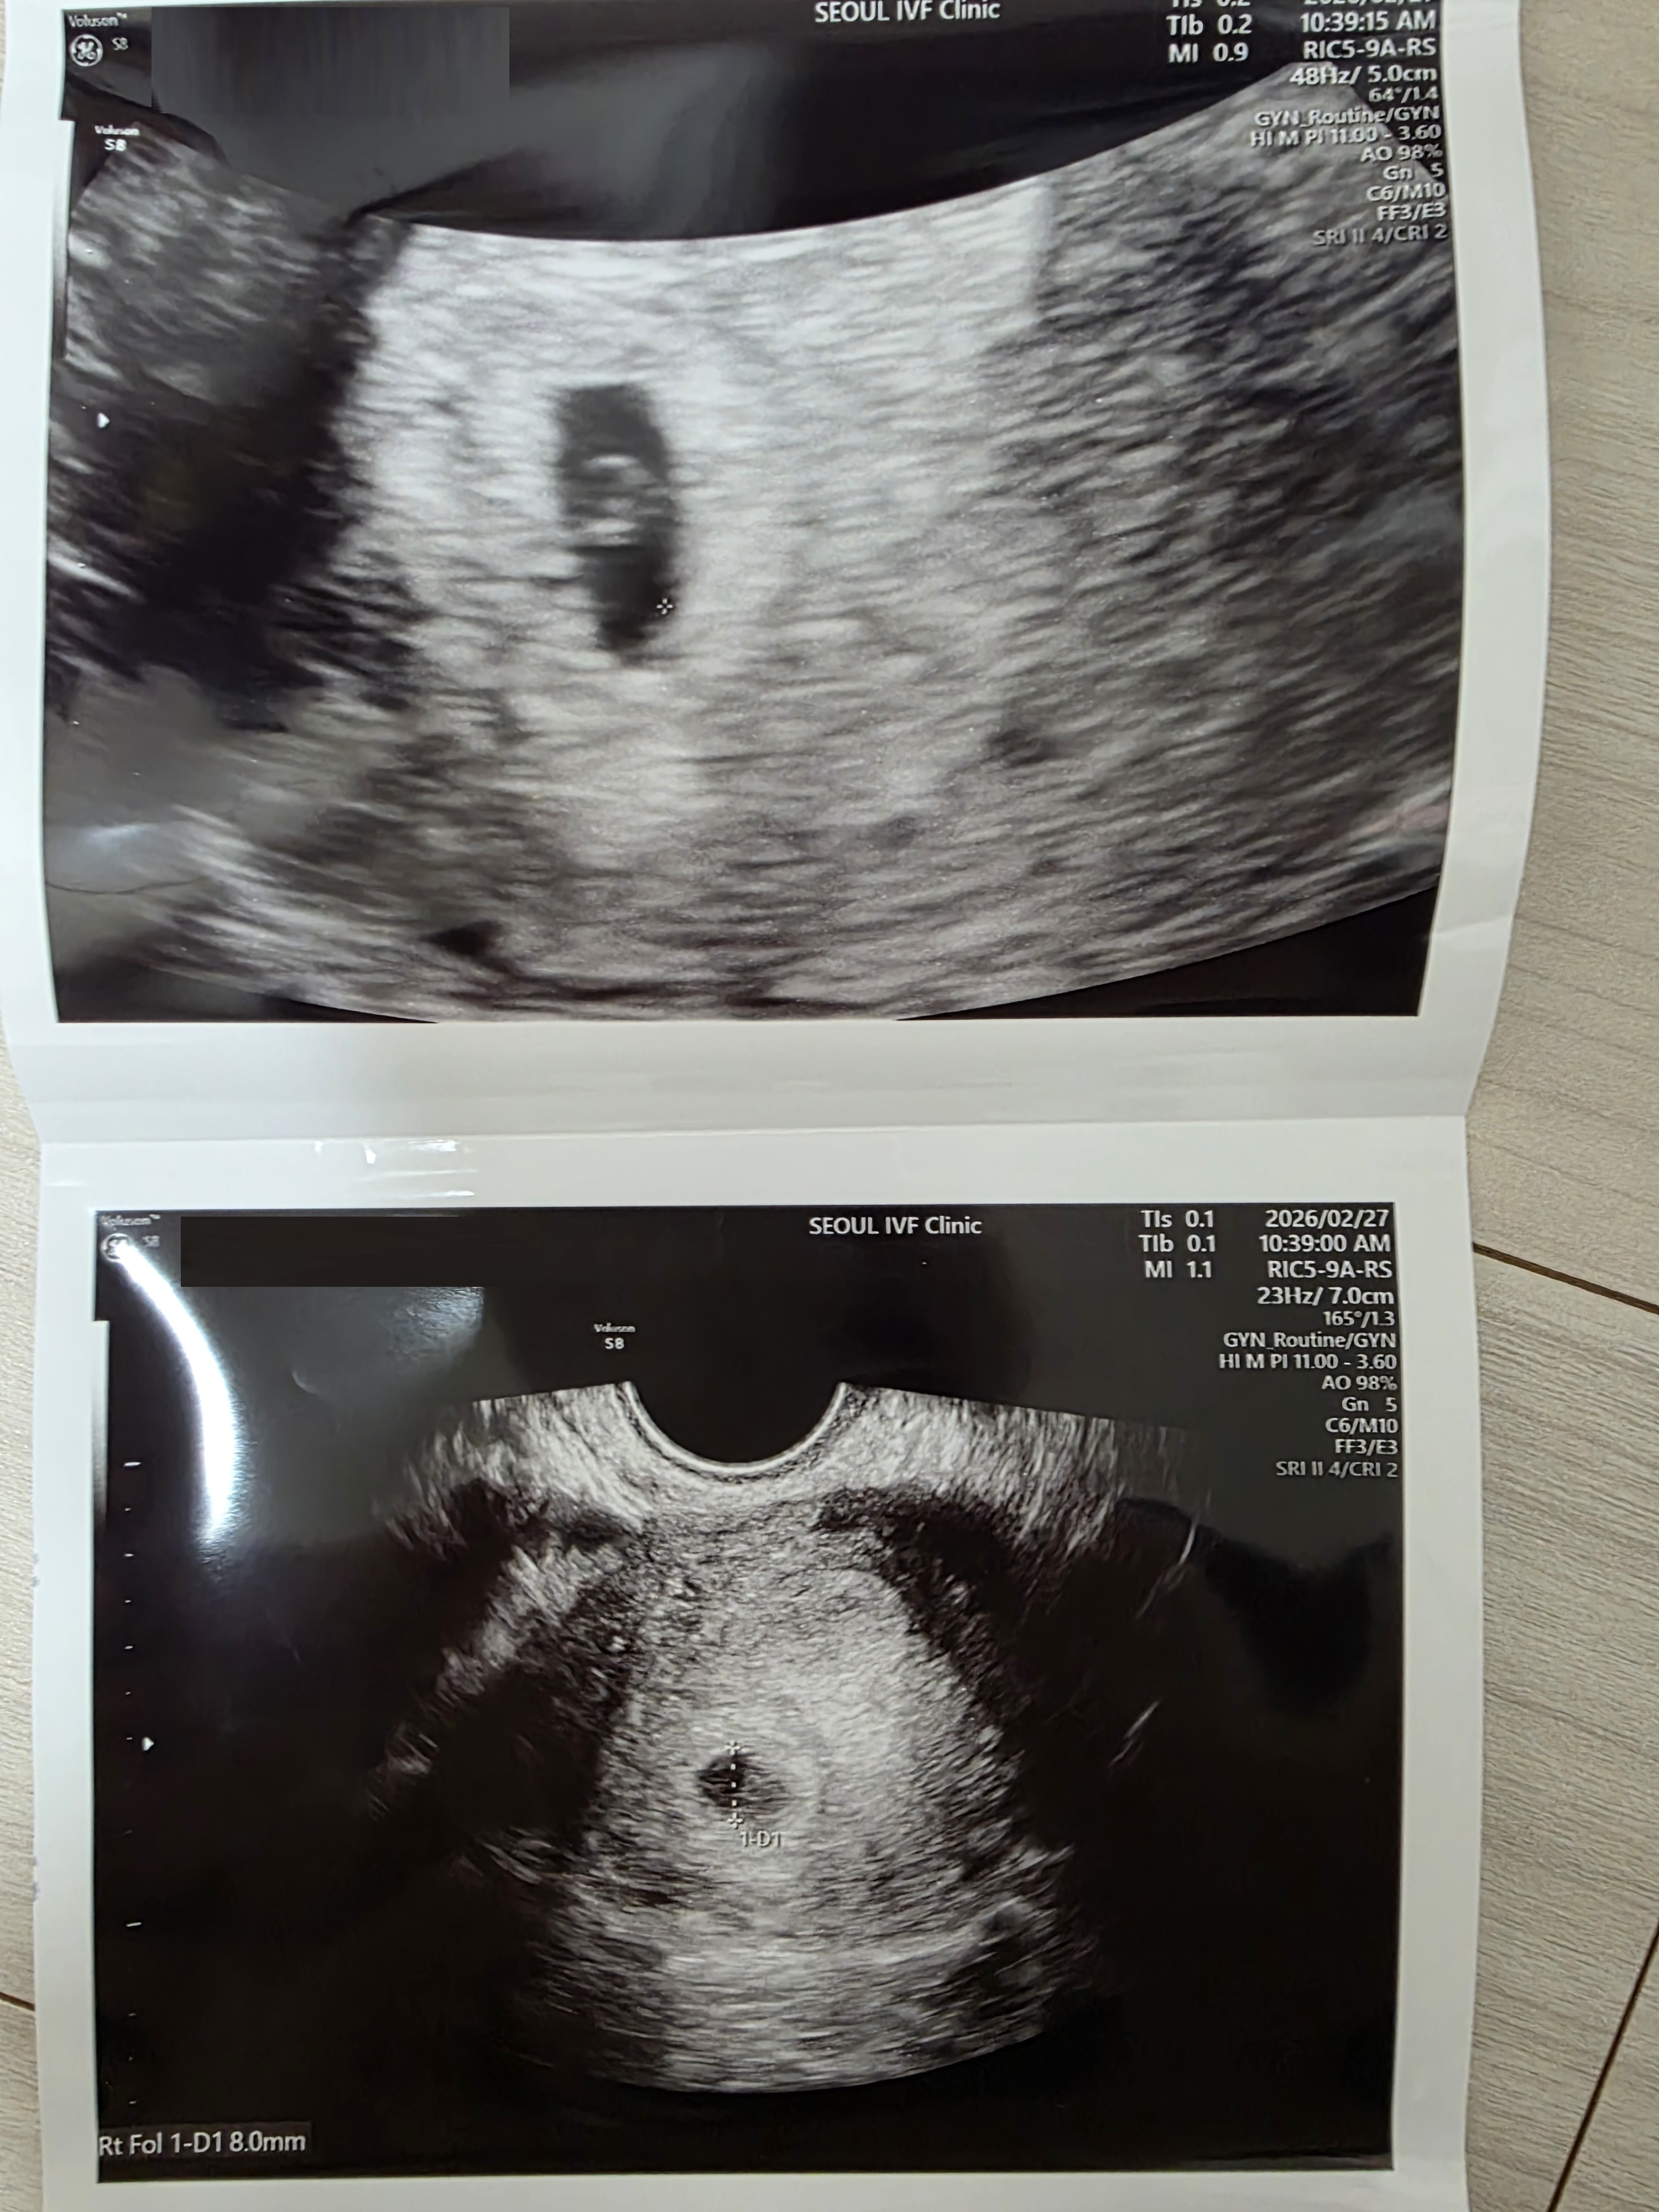

| 가슴 떨리는 임신 이야기를 공유해 주세요. | 둘째 아이를 간절히 바라는 마음으로 냉동 배아 이식을 진행하게 되었습니다. 배아 상태가 좋지 않아 큰 기대를 하지 못한 채 이식을 이어갔고, 1차, 2차 모두 화학적 임신으로 끝나며 마음이 많이 지쳤던 시간이었습니다. 이후 3차 이식을 진행했고, 1차 피검사 수치 역시 다시 화학적 임신처럼 보여 큰 기대를 하지 않았습니다. 하지만 2차 피검사에서 수치가 상승하기 시작했고, 3차 피검사에서 이경훈 원장께 “축하드립니다”라는 말을 듣게 되었습니다. 이후 아기집까지 확인하고 지금은 뱃속에서 아기가 잘 자라고 있습니다.♡ |

| 치료 도중 느꼈던 가장 기뻤던 순간과 절망적인 것들은 무엇인가요? 잊지 못할 경험이 있나요? | 가장 기뻤던 순간은 아기집을 확인했을 때였습니다. 가장 힘들었던 순간은 화학적 임신으로 이어졌던 시기였습니다. |